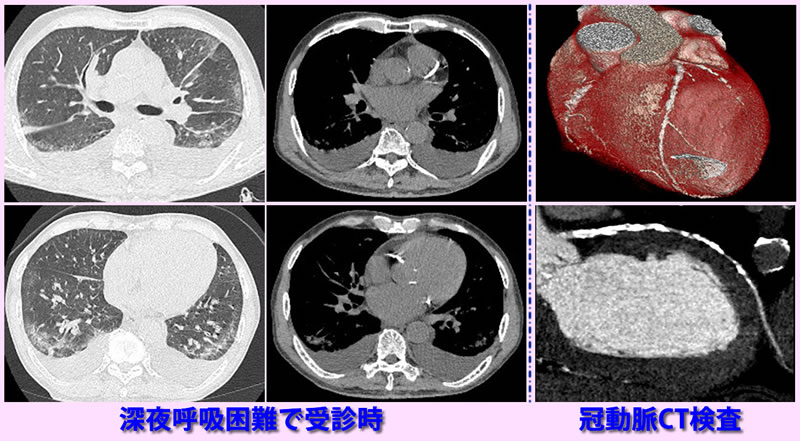

深夜2時30分トイレに行き、息苦しくなり、持続するため午前3時に受診。血液酸素飽和度70%台に低下。CTで肺水腫(左側画像)と両側の胸水貯留(中央画像)認め、酸素投与下に利尿剤使用して心不全改善。この時CTで冠動脈の石灰化認めたため、後日冠動脈CT検査施行。冠動脈3枝の著明な石灰化認め、冠動脈狭窄が心不全の原因と考えられ心臓外科紹介。冠動脈のバイパス手術行われ、現在外来通院中 虚血性心不全

夜間10時頃、息苦しさ出現。看護師付き添いで緊急受診。血液酸素飽和度70%前後、頻呼吸、呼吸困難強く、酸素投与下にCT検査。著明な肺水腫認め(左側画像)、急性心不全として,酸素投与と利尿剤投与。約2時間30分後症状改善し、帰宅。翌日確認のためCT検査実施(右側画像)。肺水腫は消失。以後外来で9年間心不全の治療と観察をしているが心不全は生じていない。

急性心不全肺水腫